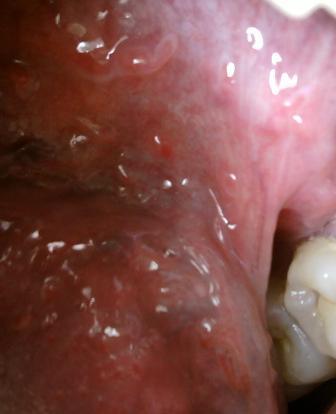

石家庄九州皮肤病医院 > 尖锐湿疣 > > > 治疗尖锐湿疣的方法以及费用?尖锐湿疣患病之后,会对人们身体健康带来比较大的危害,因此专家表示:对于疾病一定要引起重视,及时就诊才是最为关键的,现在医学上对于疾病诊治也是比较重视的。

治疗尖锐湿疣的方法以及费用?相信医学,及时对症诊治,才能够更加迅速的得以治愈。中医疗法,西医疗法以及药物诊疗,有不同的侧重点,建议采取系统的诊治方法,尖锐湿疣疾病是一种很复杂的疾病,这种疾病的出现会给很多病人带来严重的危害,所以请大家注意。